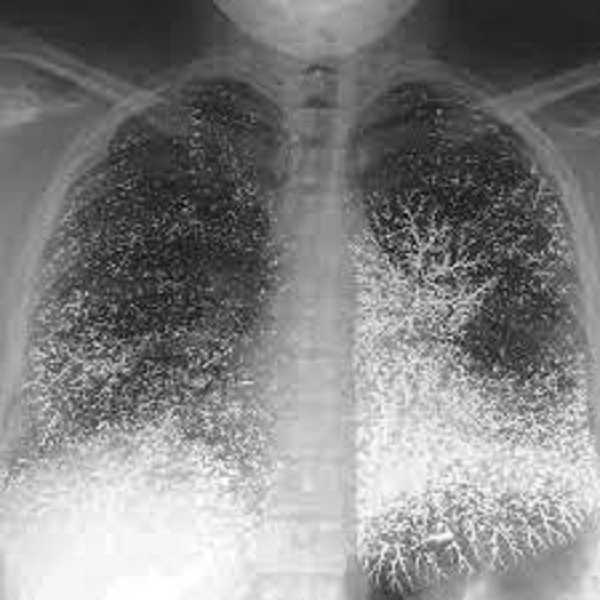

Ngay sau đó, các chuyên gia đã tiến hành mở cỗ quan tài ra và thực hiện 1 cuộc kiểm tra thân phận, cũng như nguyên nhân qua đời của chủ nhân ngôi mộ này bằng sóng điện từ.

Kết quả thu được khiến ai cũng sửng sốt, các bộ phận trên thân thể của chủ nhân ngôi mộ như phần đầu, não bộ, phần ổ bụng hay phần tay đều hiện rõ lên những vùng màu đen và những chấm đen dày đặc. Đặc biệt tại 3 vùng như bụng, tay và xương đều phát hiện 1 lượng lớn thủy ngân.

Số thủy ngân trong quan tài mà đội khảo cổ thu thập được lên đến 1,5 lít. Tuy nhiên, nguyên nhân thật sự cho cái chết của chủ nhân ngôi mộ này vẫn chưa được làm rõ.